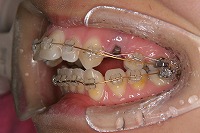

右

上の前歯が出ている事を主訴に来院された、23歳2か月の女性です。診断「下顎骨の後方回転による骨格性上顎前突で開咬を伴う」上顎は両側第1小臼歯、下顎は抜歯をせず治療を行いました。